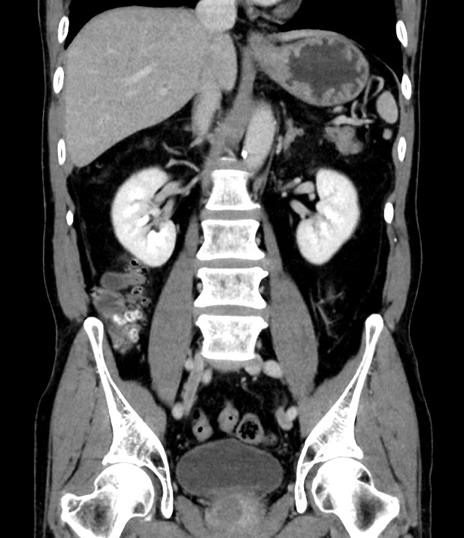

横断像